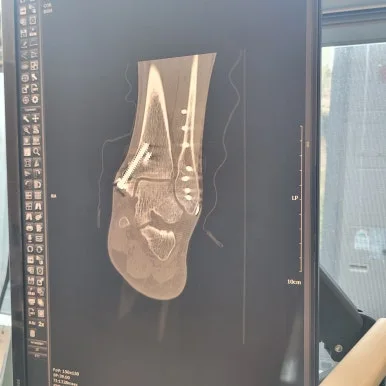

1~4월은 2024년 발목 골절 후 철심 삽입한 상태에서 러닝 했기 때문에 그다지 자유롭지는 못했지만 10km 전후로 꾸준히 재활하면서 러닝 체력을 유지하려고 애쓴 시간이었어요. 4월 25일 철심 제거 수술로 5월은 아예 달리지 못하고 회복하고 걷기만 했어요. 참 갑갑한 시간이었지만 달릴 수 있다는 게, 걸을 수 있다는 게 참 감사하는구나를 절실히 느낀 시기이기도 합니다.

2025.4.25 발목 골절 철심 제거 수술

지금도 수술 당일 마취 후 통증만 생각하면 아려옵니다. 진통제도 들지 않을 때가 있거든요. 수술 후 1~2일이 가장 힘들었고 점점 나아졌지만 아픈 시간이었어요. 그 시간을 독서로, 필사로, 글쓰기로 이겨내서 나름대로 시간도 잘 활용했어요. 그래서 그나마 덜 고통스러웠어요. 언제든지 이 순간 최선의 일은 무엇일까 생각하는 습관이 도움이 되었고 시간이 잘 가더라고요.